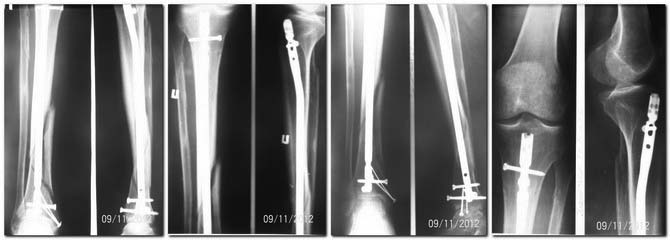

Данный случай является одним из сложных, потому что спиральный фрагмент лежит отдельно, а основные части большеберцовой расположились ввиде заточенного карандаша. Динамизация при таких явлениях редко эффективна, и для ускорения процесса прибегают к замене гвоздя.

Снимки в двух проекциях недостаточны для оценки, надо добавить дополнительные косые 45 градусные снимки. Спиральная КТ лучше покажет окружность кости, но на последних снимках идет консолидация перелома, особенно наверху. Можно подождать и продолжать нагрузку!

Здравствуйте, уважаемые коллеги.

Не так давно на форуме обсуждался случай несращения после интерлокинга инфраистмального перелома большеберцовой кости. Не хочется повторяться, но в представленном случае, с моей точки зрения, причина несращения идентична. С той лишь разницей, что перелом можно рассматривать как сегментарный и имеющий как инфраистмальную составляющую, так и супраистмальную. Повторюсь, уже имея в виду супраистмальный перелом. Два винта, проведенные во фронтальной плоскости в проксимальном отломке не всегда могут обеспечить стабильность фиксации во фронтальной плоскости, если на уровне истмуса диаметр стержня значительно меньше диаметра костномозгового канала. Особенно, если один из двух блокирующих винтов проведен через овальное отверстие. В обсуждаемом случае об истмусе, как самой узкой части костномозгового канала, говорить вообще не приходится, поскольку промежуточный фрагмент, который формировал канал на уровне истмуса, значительно смещён по ширине. Как место плотного контакта стержня и кости истмус можно исключить. В таком случае обеспечение неподвижности между стержнем и проксимальным отломком целиком зависит от проксимальных блокирующих винтов, а если быть ещё точнее, от их количества и числа плоскостей, в которых они проведены. В обсуждаемом случае перелом изначально был расценен как инфраистмальный и, совершенно обосновано, выполнено дистальное блокирование тремя блокирующими винтами в полифокальных плоскостях. Такое же блокирование, с моей точки зрения, следовало бы выполнить и в проксимальном отломке. Ещё лучше бы его выполнить четырьмя винтами. В случаях переломов типа Winquist III (данный случай) вообще рассчитывать на последующую динамизацию не разумно и, чтобы блокирующий винт в овальном отверстии выполнял бы хоть какую-то функцию при нагрузке, мы его изначально проводим по нижнему краю отверстия. Выполненная динамизация только ухудшила ситуацию, поскольку к нестабильности во фронтальной плоскости добавилась нестабильность и в сагиттальной. Если оставить всё как есть, трудно рассчитывать на положительный результат. С моей точки зрения больной нуждается в повторном оперативном вмешательстве. Трудно рассчитывать на эффект от каких-либо других способов лечения, если присутствует нестабильность в месте перелома, вызванная несостоятельность металлоконструкции. Необходим реостеосинтез . Стержень необходимо заменить, поскольку после шести месяцев существует угроза его перелома из-за усталости металла при последующей нагрузке. Поскольку истмуса нет, диаметр нового стержня не имеет принципиального значения. Он может быть таким же. Принципиальное значение имеет адекватное блокирование, как в дистальном, так и проксимальном отломке. Рассверливание канала необходимо только как способ получения пластического материала. И самое важное. Больному должна быть рекомендована полная нагрузка на ногу сразу после операции. Без неё интерлокинг теряет многие свои преимущества как метод остеосинтеза.